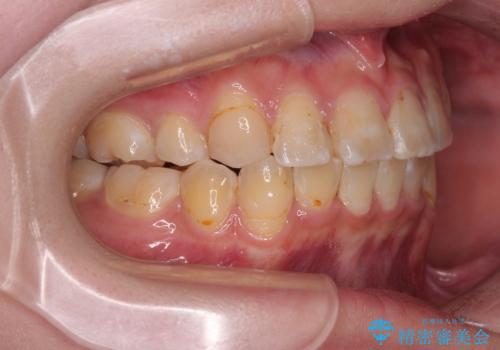

転位歯や埋伏歯などの難易度の高い抜歯矯正治療

- 八重歯や埋伏している奥歯など、多くの難しい問題を抱えている患者様です。

重度叢生のため、大臼歯をしっかりと咬合させるために、下顎は左右第二小臼歯を、上顎は前歯部の叢生を解消するために左右第一小臼歯を抜歯し、口元の突出感を改善するために、上顎大臼歯が前方に移動しないようにするために、補助装置による架強固定を行うこととしました。

叢生は思ったよりも早期に改善されましたが、舌の突出癖による上下前歯の非接触が全く改善されず、2年間ほど治療期間が延びる結果となってしまいました。